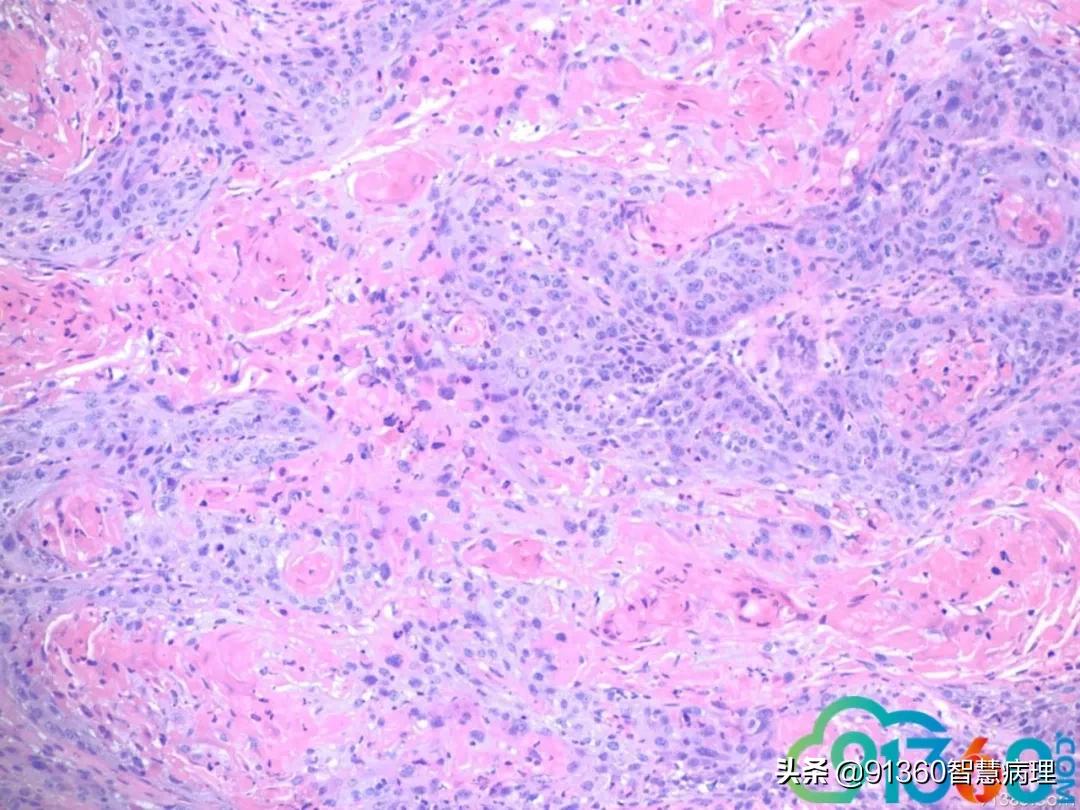

喻明芙 和Pap 符合@赵澄泉UPMC 谢谢 赵澄泉 组织切片有假象,但局部可有明显浸润 喻明芙 这就是Pap中看到的异常角化细胞

喻明芙 @赵澄泉UPMC 先给大家机会看看组织学@赵澄泉UPMC 谢谢分享 赵澄泉 @阎培莎 @诸城市妇幼保健院王瑞辉 群管 @姜锦贵,江苏金湖医院 @喻明芙/病理/康州 @彭振武(广州安必平公司) @厦门motic孙煜昀 @廖新波(JMC-NY) @舒兰市中医院病理科宋晓华 细胞学是atypical parakeratosis cells. 这是为什么大家觉得很难报LSIL, HSIL, cancer, even ascH. 经验:如果这种细胞很多尤其HPV阳,一定要想着鳞癌的可能,一定和临床沟通,组织活检,不要漏掉病人,这例我报的ASCH,备注强调病人需活检。实际工作中组织学对照是学习细胞学最好老师 石丽华 @赵澄泉UPMC 学习了谢谢老师分享这种角化不认识,实际工作中易漏掉 孙煜昀 乳头状的鳞状上皮病变,低级别时也可以出现出现这种细胞形态。两者鉴别主要是坏死和里面混杂高级别细胞,赵老师给的病例细胞学没有明确高级别细胞,报ah可以。但是要打的更高,可能需要更多视野的支持 Andy K (纽约) 这种dyskeratotic cells是高度怀疑鳞癌的

喻明芙 我学习的麟癌有3大特征:肿瘤素质(非常难认),异常角化,和异形麟装上皮有核仁。反过来看,这里Pap缺第三,但要怀疑。我会写到Note 孙煜昀 支持老师看法红圈的细胞对照的很好,绿圈的细胞在细胞学没有对应,只有我打剪头的一个细胞,所以才加大了难度可能在肿瘤表面全是角化不全的细胞。很难取到下面的肿瘤主体